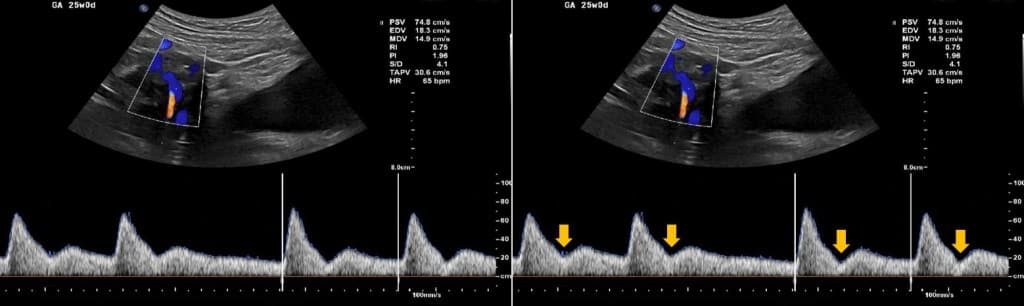

Por fim, o Doppler das artérias uterinas avalia o compartimento materno da placenta, fornecendo informações sobre a resistência vascular uterina e o funcionamento das artérias espirais.

Durante a gestação normal, a invasão trofoblástica no primeiro trimestre promove o remodelamento dessas artérias, o que, consequentemente, reduz sua resistência e garante suprimento adequado à placenta. No entanto, alterações nesse processo, como resistência aumentada ou presença de incisura diastólica bilateral, estão associadas a um maior risco de pré-eclâmpsia (PE) precoce e restrição de crescimento fetal (RCF).

Nesse contexto, utiliza-se o índice de pulsatilidade (IP) das artérias uterinas para quantificar essa resistência, sendo valores elevados indicativos de risco aumentado.

Além disso, a presença de incisura protodiastólica sugere fluxo mais restrito, e seu achado precoce no primeiro trimestre pode ajudar na triagem de gestantes de alto risco, permitindo intervenção e monitoramento adequado.